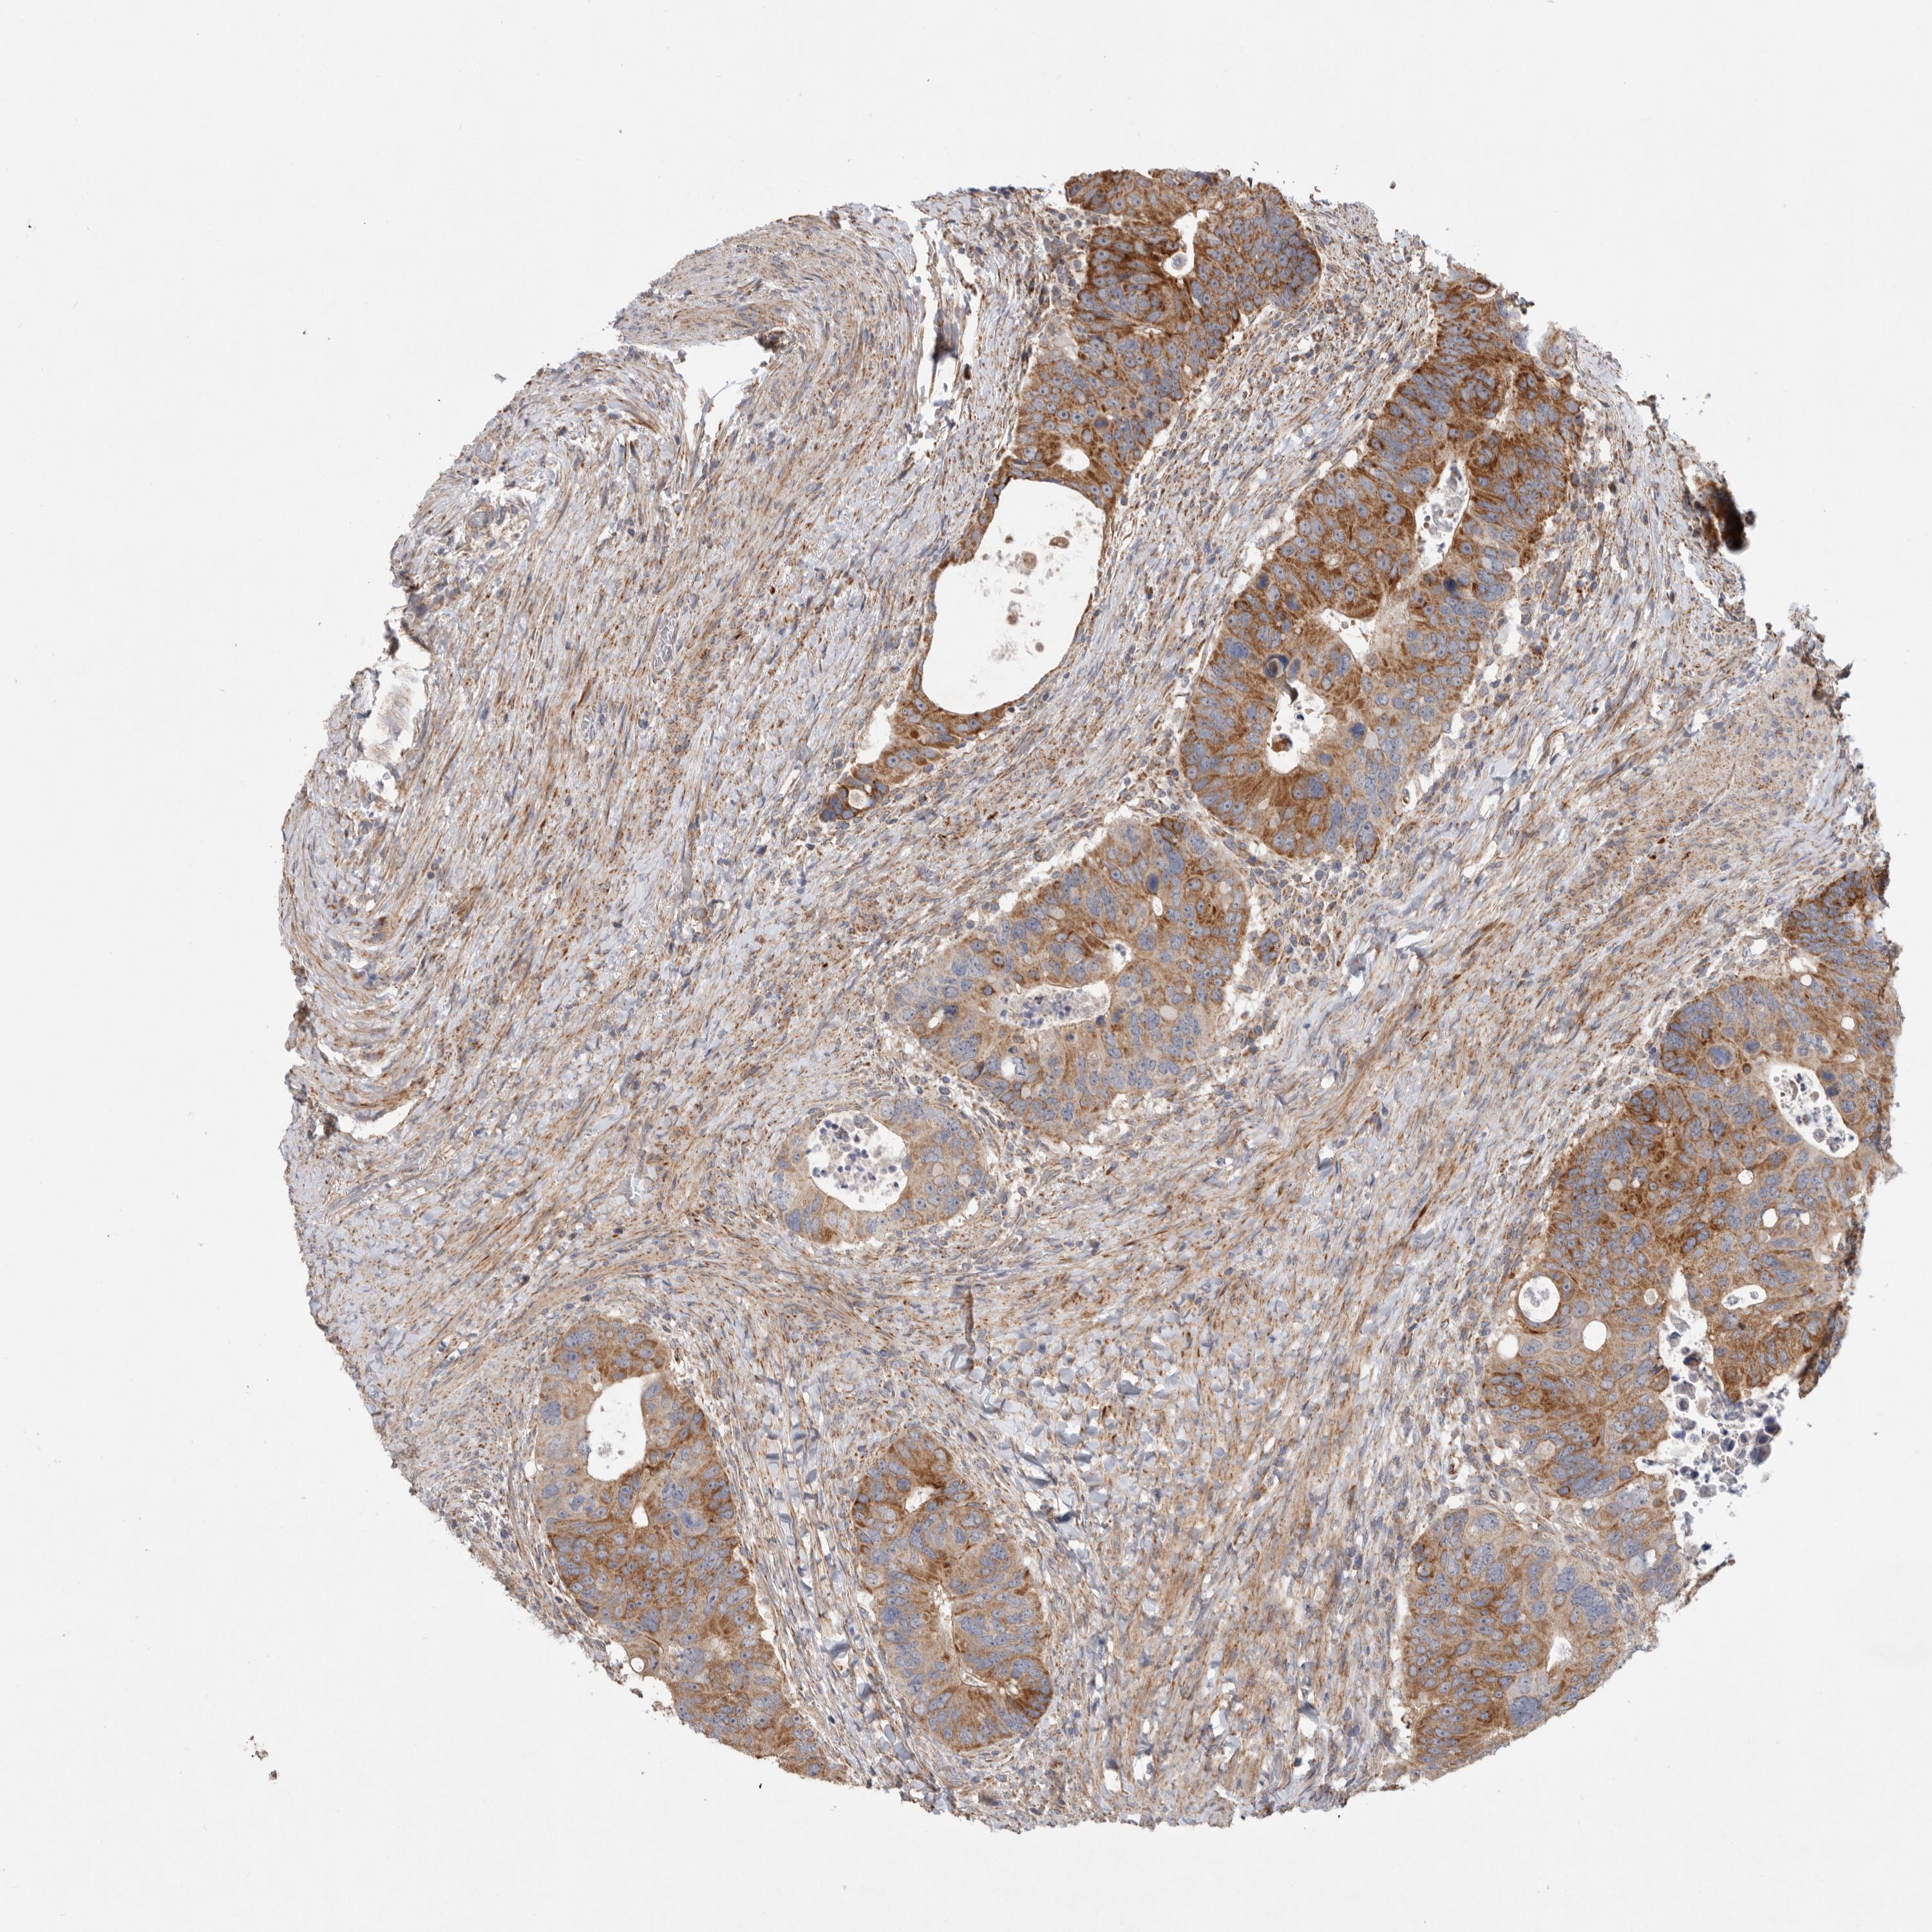

CANCER COLORECTAL CANCER Show tissue menu

Colorectal cancer

Human cancer

Colon adenocarcinoma